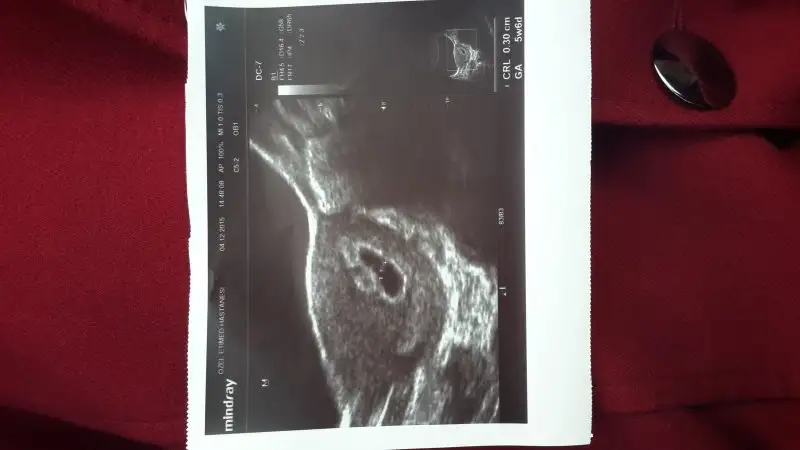

Foto atınmerhaba sekiz haftalik hamileyim bebis tam ortada ne sag ne sol sizce nedir

Sola yakın erkek gibi emirardam

ama plasenta sol altta değil mi ben mi yanlış gördüm. şayet ultrason karındansa erkek olması gerekli değil miBen bu görüntüde kız diorm. Benim görüşüm farklı

benim resmim icinmi kız dedinizBen bu görüntüde kız diorm. Benim görüşüm farklı

hayırlı akşamlar arkadaşlar bu gün cinsiyet kesinleşti oğlum olacakmış hepinize teşekkürler tahminlerinin için![]()